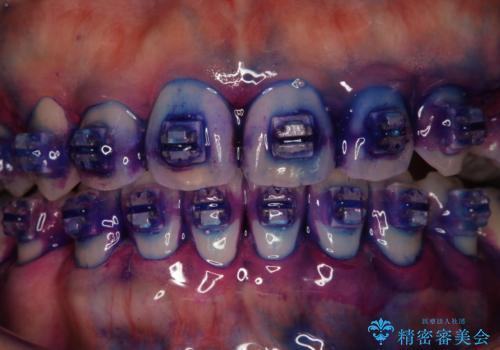

ワイヤー矯正中に歯の染め出し

- ワイヤー矯正中にクリーニンング希望とのことでした。染め出しを行い歯磨き指導とPMTC60分コースを行いました。

ワイヤー矯正中はブラッシングが難しくなるため、磨き残しが多くなることがあります。適切な道具を使って、適切なブラッシング方法を習得することで、磨き残しを減らすことができます。

また、矯正で歯の移動があると今までなかったところに隙間が出てきたり、ガタつきが解消されてきたりすることで、お口の中の環境が変わります。